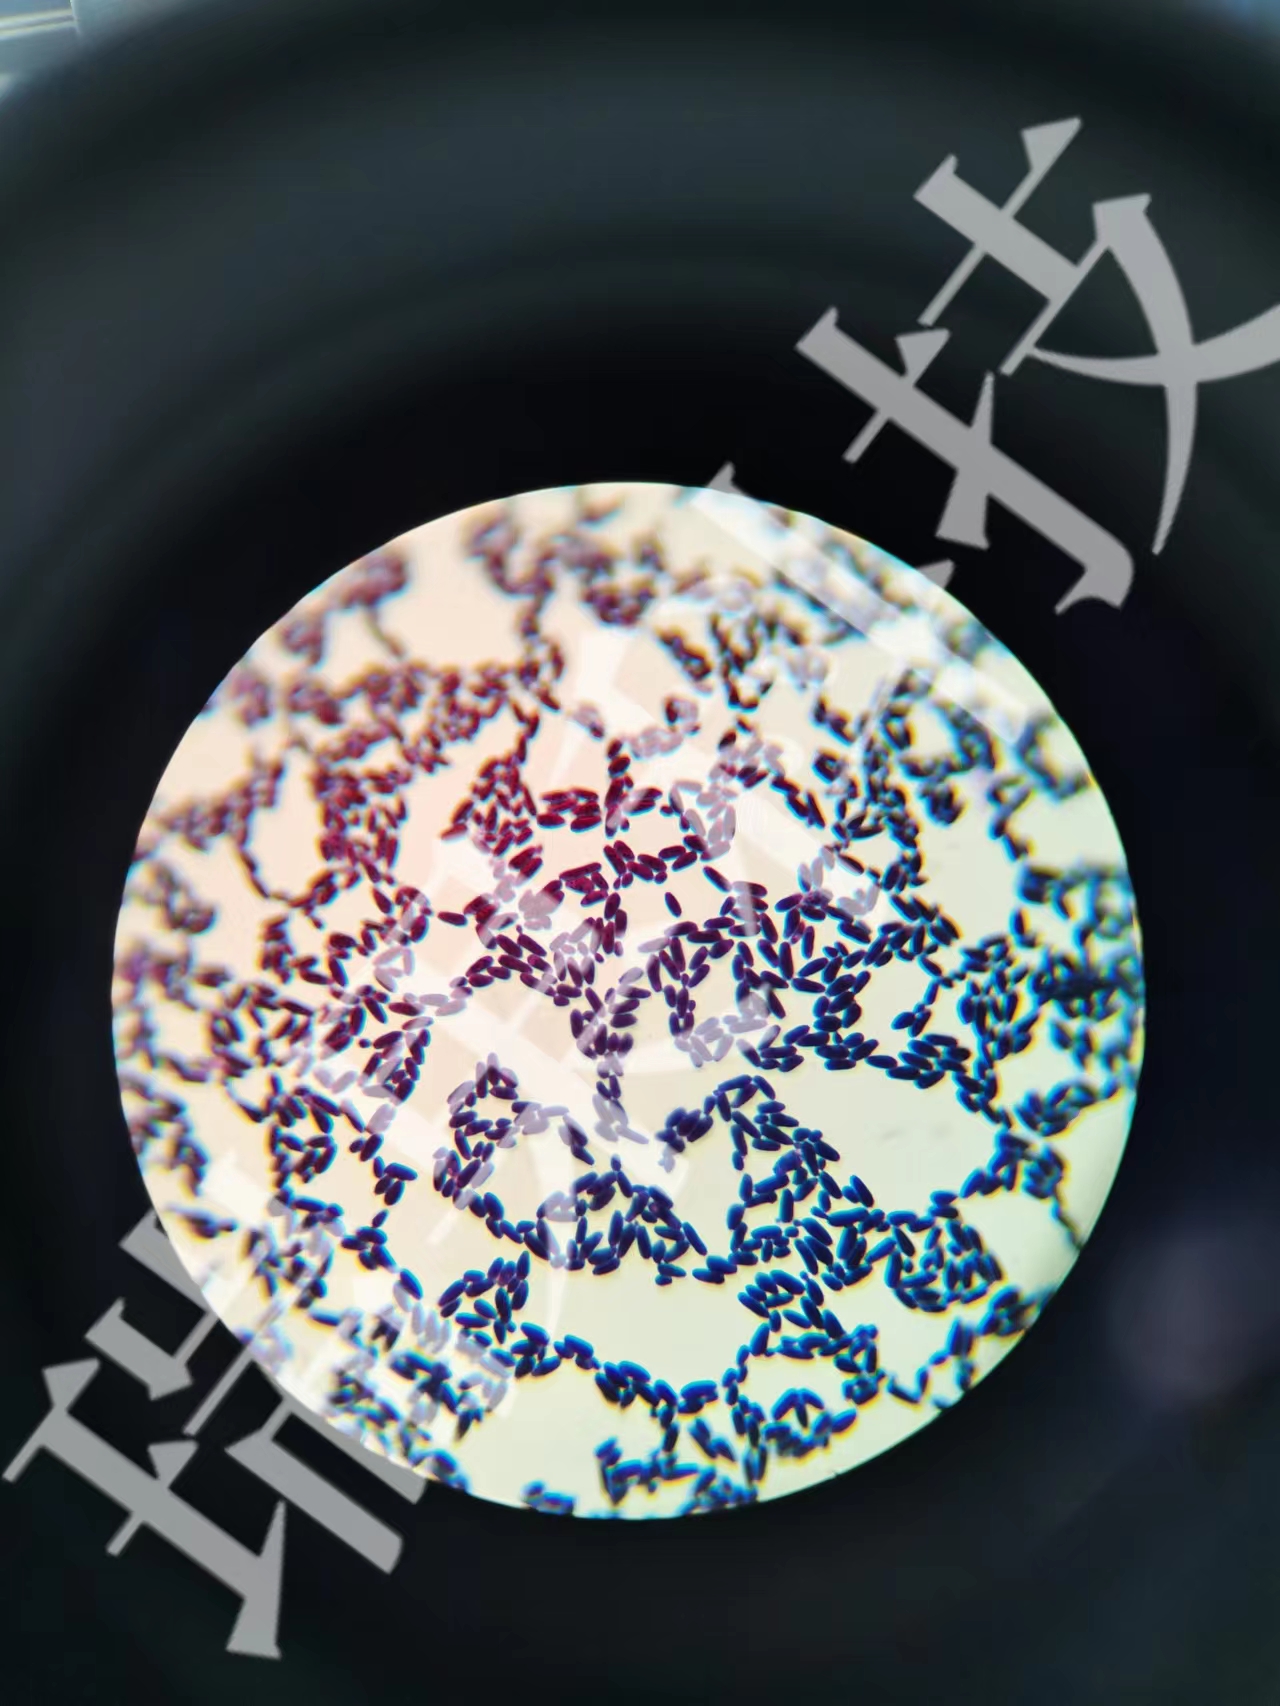

过碘酸-雪夫(Pexiodic acid-schiff,PAS)染色又称糖原染色。胞浆内存在的糖原或多糖类物质(如黏多糖、黏蛋白、糖蛋白、糖酯等)中的乙二醇基(CHOH-CHOH)经过碘酸(Periodic acid)氧化,转变为二醛基(CHO-CHO),与雪夫(Schiff

过碘酸-雪夫(Pexiodic acid-schiff,PAS)染色又称糖原染色。胞浆内存在的糖原或多糖类物质(如黏多糖、黏蛋白、糖蛋白、糖酯等)中的乙二醇基(CHOH-CHOH)经过碘酸(Periodic acid)氧化,转变为二醛基(CHO-CHO),与雪夫(Schiff)试剂中的无色品红结合,形成紫红色化合物而沉积于胞浆中糖原类物质所存在的部位。该反应称为过碘酸-雪夫(PAS)阳性反应。